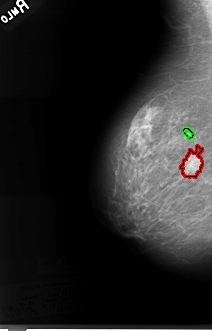

FILE: B_3060_1.RIGHT_MLO.OVERLAY

TOTAL_ABNORMALITIES 2

ABNORMALITY 1

LESION_TYPE MASS SHAPE IRREGULAR-ARCHITECTURAL_DISTORTION MARGINS SPICULATED

ASSESSMENT 4

SUBTLETY 5

PATHOLOGY MALIGNANT

ABNORMALITY 2

LESION_TYPE CALCIFICATION TYPE PLEOMORPHIC DISTRIBUTION CLUSTERED

SUBTLETY 4

PATHOLOGY UNPROVEN